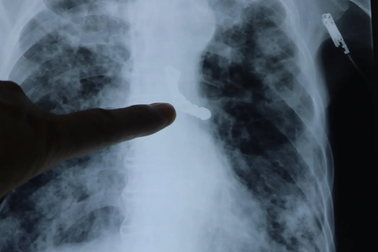

Răng giả mắc kẹt trong phổi của người đàn ôngBác sĩ ở tỉnh Khánh Hòa vừa tiến hành nội soi và lấy thành công dị vật là một răng giả ra khỏi phổi của nam bệnh nhân.

Súc miệng đi ngủ, cô gái suýt chết vì rơi răng giả xuống phổiTrong lúc súc miệng đi ngủ, chiếc răng giả có 3 móc sắt của cô gái rơi xuống cổ họng, khiến nạn nhân ho sặc sụa, đau tức ngực kéo dài phải nhập viện cấp cứu.

Cụ ông tắc đường thở vì 9 chiếc răng giả chui tọt vào phế quảnNgày 14/8, bệnh viện Phổi Trung ương cho biết vừa cấp cứu kịp thời ca bệnh bị rơi cả cầu răng giả gồm 9 chiếc răng vào phế quản, khiến người bệnh khó thở, đe dọa tính mạng.